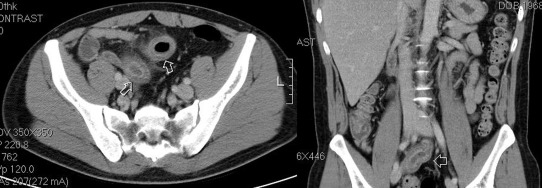

An esophagogastroduodenoscopy (EGD) showed erosive esophagitis, Los Angeles classification Grade A, and gastritis over antrum. An abdominal computed tomography (CT) showed an edematous change of the intestinal wall and the distal part of the ileum (Fig. 2 ). Empiric antibiotics with ciprofloxacin were prescribed for possible ileitis. A retrograde single balloon enteroscopy (SIF-260, Olympus Medical Systems, Tokyo, Japan) revealed several 0.5–1.5 cm discrete shallow ulcers and hyperemic mucosa at the distal ileum. The middle, proximal, and terminal ileum and the ileocecal valve to the rectum were not affected (Fig. 3 ). Chromoendoscopy with 0.2% indigo carmine dye demonstrated edematous hyperemic intestinal villi (Fig. 4 ). An endoscopic biopsy specimen of ileal ulcers showed chronic inflammation. The creatinine level was 76.9 μmol/L (normal range 61.88–106.08 μmol/L). The platelet level was 379 × 103 /μL (normal range 150–450 × 103 /μL).

An abdominal computed tomography shows edematous changes to the intestinal wall ...

An abdominal computed tomography shows edematous changes to the intestinal wall and the distal part of the ileum.